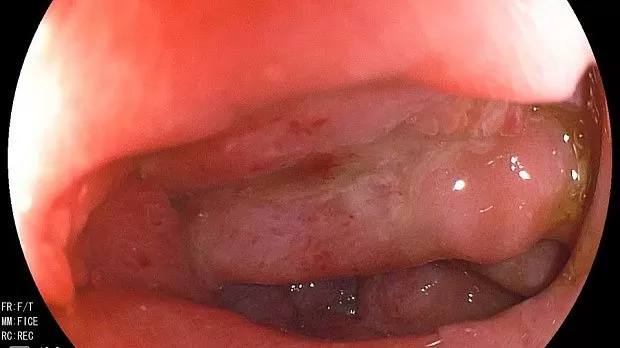

Эндоскопия выполнена 22.06.2016 - залуковичный отдел – просвет циркулярно сужен до 1.0см, слизистая гиперемирована, отечная, при инструментальной пальпации плотно-эластической консистенции. Papilla Vateri: втянут в отечные складки, дольчатой структуры обычных размеров и формы, желчь в ДПК поступает с примесью белесоватой жидкости (гной). Учитывая данные анамнеза, инструментальных методов исследований (КТ) у пациента можно предположить.

ЗАКЛЮЧЕНИЕ: Гетеротопия ткани поджелудочной железы в нисходящую ветвь ДПК, с стенозированием просвета I степени. Холангит.